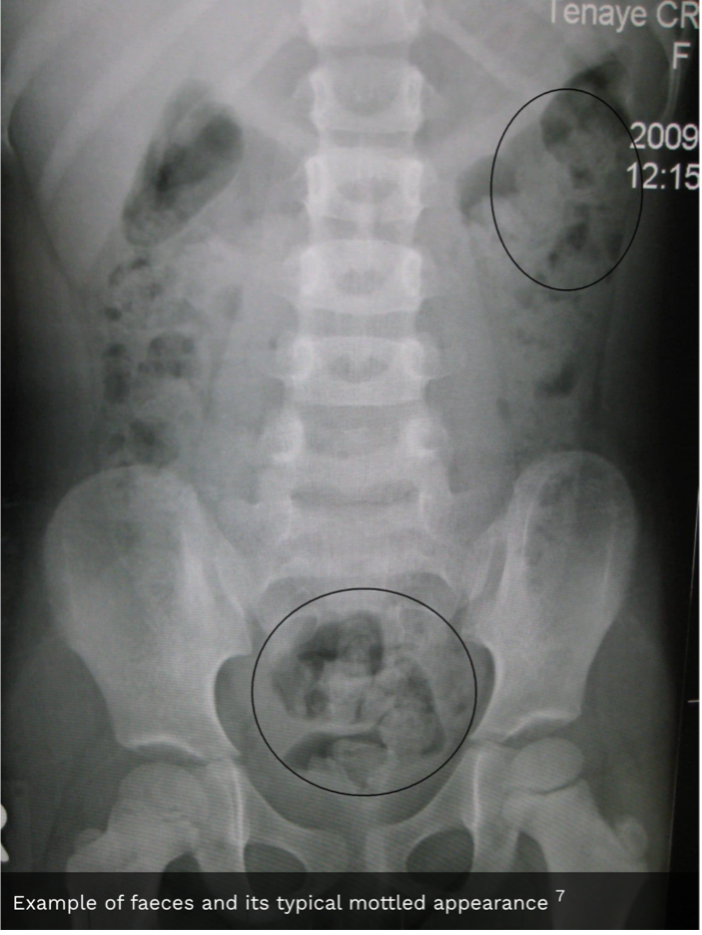

18

Give the appearance of faeces on an AXR

A

Faeces have a mottled appearance due to trapped gas in colon.